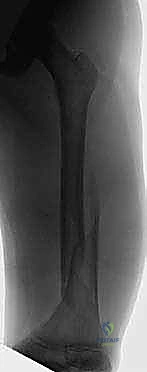

Clinical & Radiographic Imaging